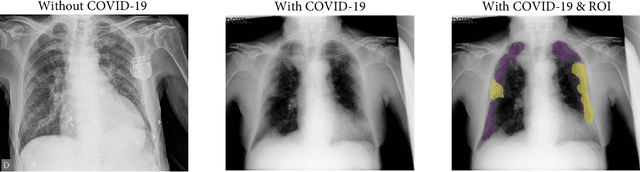

Abstract:There is a necessity to develop affordable, and reliable diagnostic tools, which allow containing the COVID-19 spreading. Machine Learning (ML) algorithms have been proposed to design support decision-making systems to assess chest X-ray images, which have proven to be useful to detect and evaluate disease progression. Many research articles are published around this subject, which makes it difficult to identify the best approaches for future work. This paper presents a systematic review of ML applied to COVID-19 detection using chest X-ray images, aiming to offer a baseline for researchers in terms of methods, architectures, databases, and current limitations.